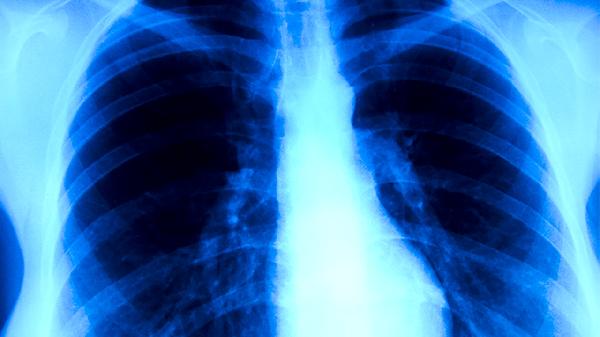

非开放性肺结核怎么回事,怎么办

非开放性肺结核可能由结核分枝杆菌感染、免疫力低下、接触传染源、营养不良、慢性疾病等因素引起,可通过抗结核药物治疗、营养支持、隔离防护、定期复查、手术治疗等方式治疗。

非开放性肺结核患者应保持规律作息,每日保证8小时睡眠,避免过度劳累。饮食上注意荤素搭配,多摄入新鲜蔬菜水果,限制辛辣刺激性食物。康复期间可进行散步、太极拳等低强度运动,但需避免人群密集场所。严格遵医嘱完成6-9个月药物治疗疗程,不可自行减药或停药,治疗期间每月复查胸部影像学和痰菌检查,密切监测肝功能等指标变化。